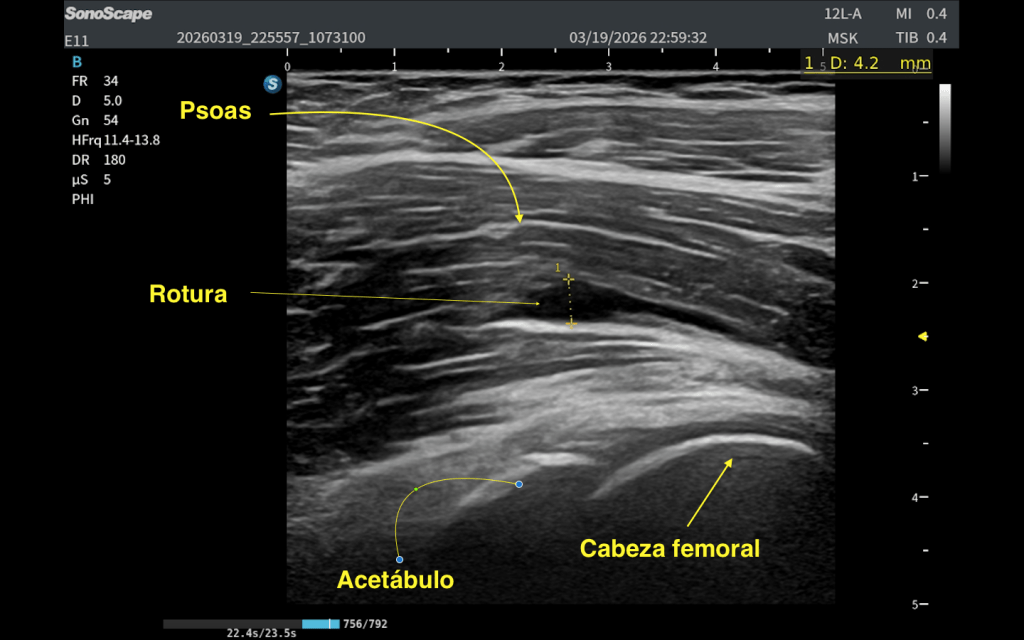

A nivel de la cabeza femoral izquierda, en la región profunda del psoas ilíaco, se identifica:

En eje longitudinal (eje largo – línea roja): Imagen anecoica alargada Localizada en las fibras profundas del psoas Con una longitud aproximada de 2,5 cm En eje transversal (eje corto – línea amarilla): La lesión se reproduce claramente, confirmando su existencia siempre en dos ejes. Si no lo veo en 2 cortes, no existe.

👉 La visualización en ambos planos es clave para confirmar que no se trata de un artefacto.

Rotura de las fibras internas posteriores del psoas ilíaco izquierdo, con colección anecoica compatible con hematoma.